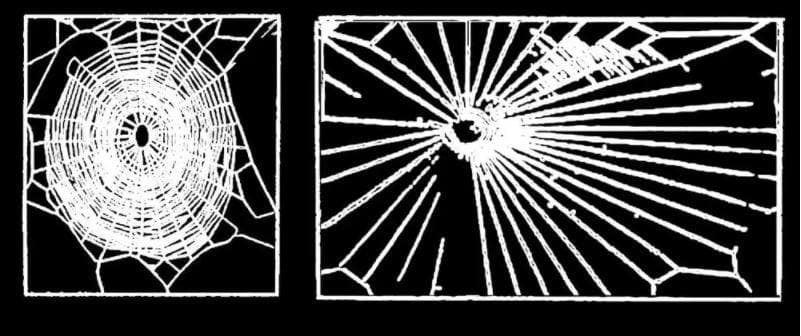

1948 年,瑞士藥理學家Peter N. Witt研究精神活性藥物對蜘蛛的影響,包括安非他命、麥斯卡林、LSD 和咖啡因,發現這些藥物會影響網的大小和形狀,變得不規則。1995 年NASA的一個研究小組復刻了Witt的實驗,質量上與 Witt 的結果相似,但新穎之處在於,蜘蛛網的模式被現代統計工具定量分析,並被提議作為一種靈敏的藥物檢測方法。